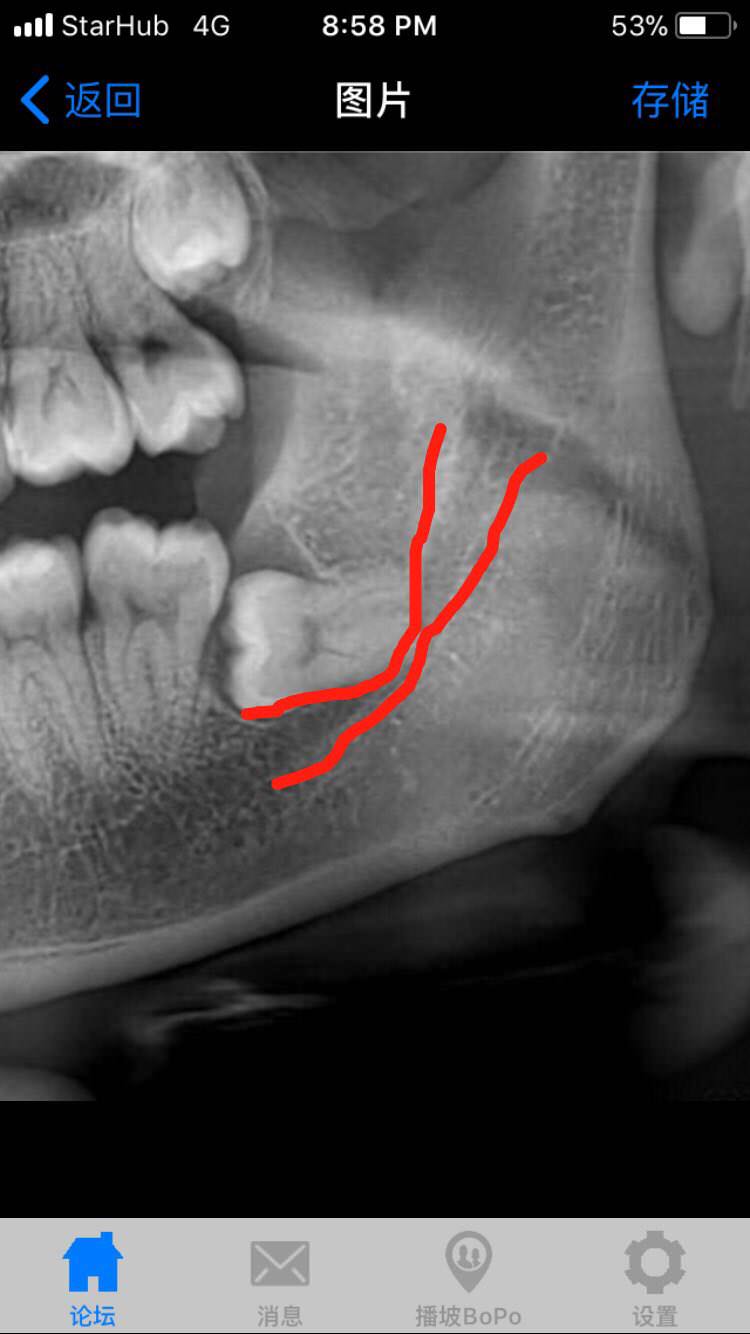

还是谨慎点 拔不好一辈子的事是不是上面那条神经已经被压的很多了

lz的跟我的一模一样啊横生,牙根勾神经。运气好的可以买toto…

必须要拔因为阻生齿会一直横长,把牙顶的不齐,而且阻生齿旁边的大牙会被顶个窟窿,越晚拔后面影响越大。所以必须拔。